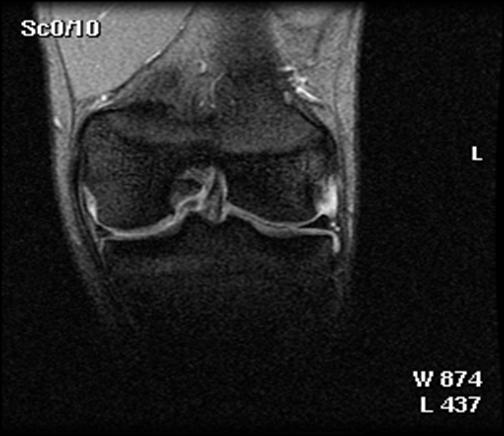

Fig.32. Imagine RMN pacient T.C. 19 ani

Fig.33. Imagine RMN T.C. 19 ani

Fig.34. A-scanare inaintea microfracturarii, B-scanare la patru luni dupaa microfracturare.

Evaluarea imaginilor RMN a fost realizata de catre radiologist cu experienta, care cunostea situatia pacientilor si operatia efectuata. Imaginile au fost astfel analizate incat sa se observe zonele cu cartilaj de reparare comparativ cu cel nativ. Repararea morfologica a fost descrisa ca depresiva, neteda, sau mareata comparativ cu cartilajul nativ inconjurator. Volumul de umplere al defectului cu cartilaj reparator a fost masurat folosind imagini sagitale si coronale si a fost gradat ca bun (intre 67% si 100%), moderat (34% la 66%), sau slab (0% la 33%) pe baza procentajului defectului umplut. Interfata cu suprafata cartilajului nativ adiacent a fost evaluata si gradata ca fiind mica ( gaura ≤ 2mm) sau mare (gaura ˃ 2mm). Edemul maduvei osului subcondral a fost gradat ca fiind usor (˂ 1 cm²), moderat (intre 1 si 3 cm²) sau sever (˃ 3 cm²), iar prezenta sau absenta cresterii osoase a fost atent inregistrata.

Din 48 de pacienti tratati cu tehnica de microfracturare in studiul nostru , 24 (50%) au acceptat sa fie evaluati prin imagini ale rezonantei magnetice. RMN a fost facuta doar pentru studiu si nu datorita vreunui simptom clinic si s-a efectuat in medie la 12 2 luni (de la 3 la 36 de luni) dupa operatie. Imaginile au fost executate la mai putin de 6 luni pentru 3 pacienti (13%), de la 6 la 12 luni pentru 15 pacienti (61%) si mai mult de 12 luni dupa microfracturi pentru 6 pacienti (26%). Sase pacienti au o serie de imagini RMN cu media 1,3 0,1 (de la 1 la 3 scanari) pe pacient. La acesti 6 pacienti, descoperirile la cea mai recenta evaluare imagistica au fost folosite pentru analiza rezultatelor functionale. Nu s-au gasit diferente semnificative intre pacientii cu sau fara evaluare imagistica RMN cu privire la datele demografice (p> 0,650); caracteristicile leziunilor (p>0,450); durata preoperatorie a simptomelor (p= 0,793); indexul masei corporale (p= 0,217); durata urmarii postoperatorii (p= 0,902); si scorul preoperator si postoperator pentru activitatile zilnice(p=0,250); SF-36componenta fizica (p= 0,250), IKDC (p= 0,820) si rata subiectiva (p = 0,867).